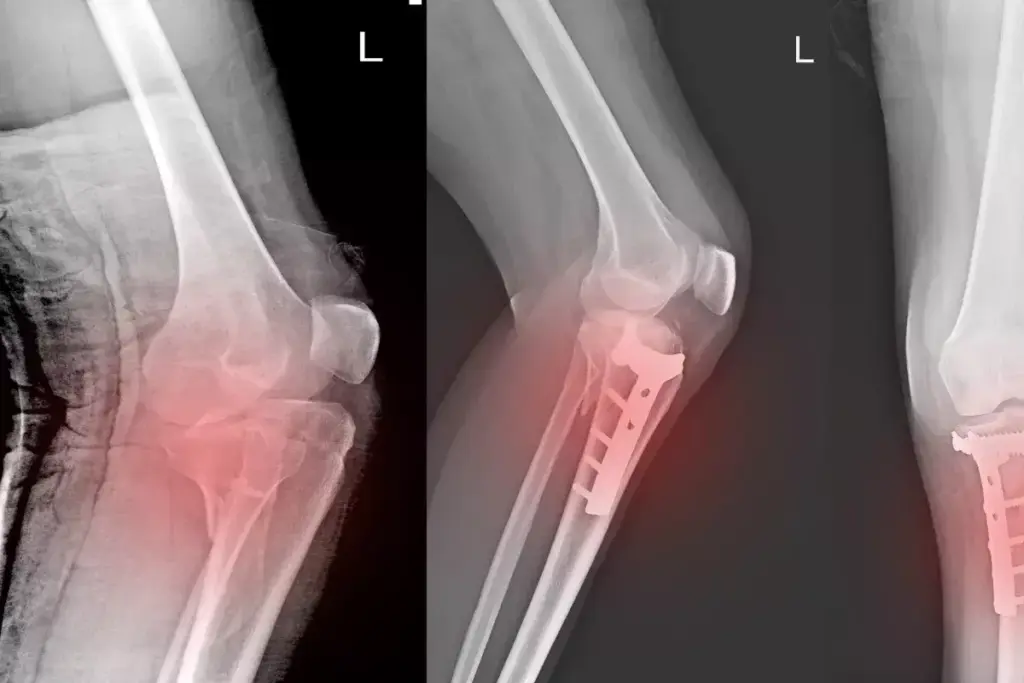

Bone grafting is a surgery to fix damaged or sick bones, like the femur. It moves bone tissue to help heal and fix the bone.

A bone graft is a surgery to move bone tissue to fix or rebuild bones. Autografts, using the patient’s own bone, are the best because they help bones grow and heal well.

The femur, a key bone, needs strong repair. Bone grafting gives it the support it needs and helps new bone grow. The graft helps new bone tissue grow and joins with the old bone.